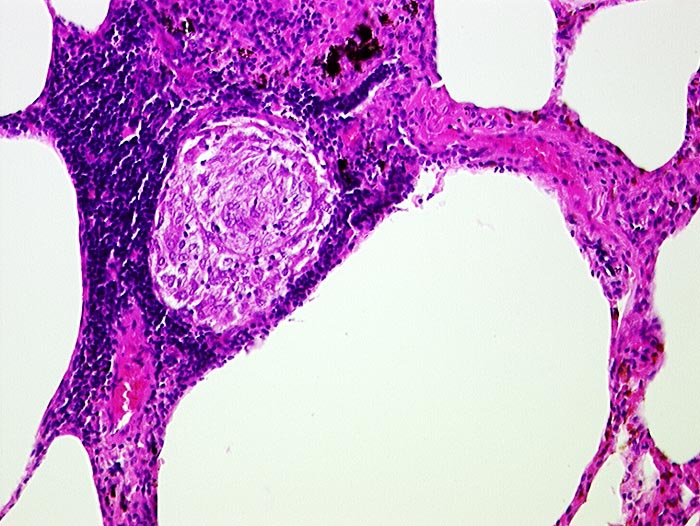

Aetiologie: Bei der Sarkoidose (Morbus Boeck) handelt es sich um eine Multisystemerkrankung mit nicht verkäsenden epitheloidzelligen Granulomen ( 706), deren Ätiologie unbekannt ist. Sowohl genetische Faktoren als auch Umweltfaktoren scheinen eine Rolle zu spielen. Möglicherweise handelt es sich um eine übertriebene zelluläre Immunantwort auf ein unbekanntes Antigen. Bisher konnte aber kein Krankheitserreger mit der Sarkoidose assoziiert werden. Die Sarkoidose ist weder eine maligne noch eine Autoimmunerkrankung.

Morphologie: Die Morphologie der Erkrankung ist stadienabhängig. Initial findet sich eine lymphozytenreiche Alveolitis mit wenigen kleinen Granulomen. Die Granulome bestehen aus Aggregaten epitheloider Histiozyten teilweise mit Beteiligung von mehrkernigen Riesenzellen. Im Verlauf entwickeln sich zellreiche Granulome entlang der bronchovaskulären Bündel und der Interalveolarsepten, welche später konfluieren und vernarben. Die Riesenzellen können Asteroidkörperchen (sternförmige Kristalle) oder Schaumannkörperchen (lamelläre Verkalkungen) enthalten. Ein Teil der Patienten entwickelt eine irreversible Lungenfibrose.